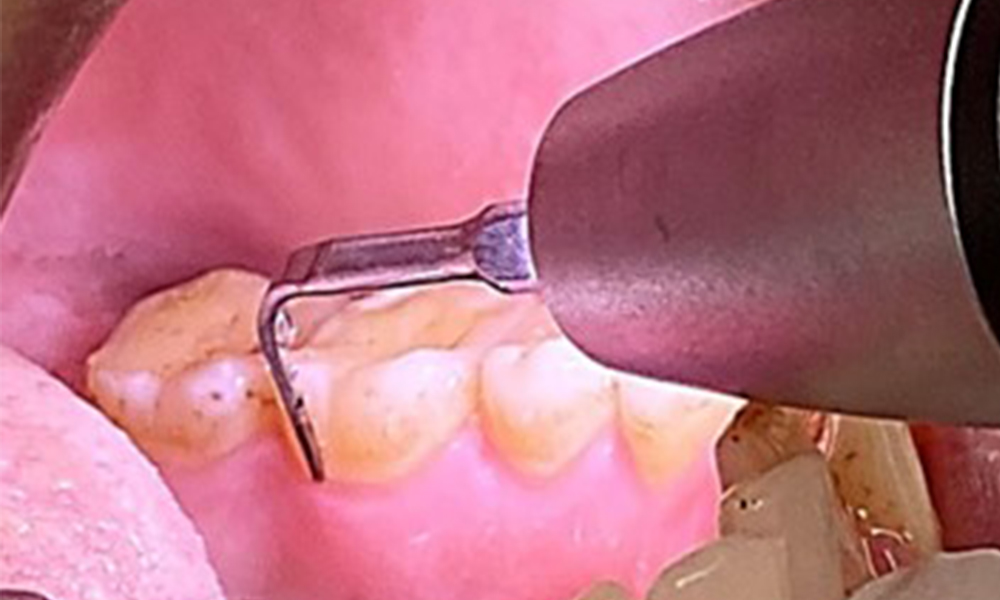

Due to the otherwise favourable general medical condition, the needs determined during the intraoral examination will be decisive for their treatment. It will be essential to periodically determine the probing depths. Gingival bleeding decreases in smokers, which is why the clinical diagnosis of periodontitis can only be made by probing (Fig. 7). Placing exclusive focus on the determination of bleeding indices may obscure existing periodontitis or gingivitis. (5)

The periodontal status should be thoroughly examined once a year. The detection of plaque using a staining agent may be a source of motivation. The assessment of intraoral findings, buccal surfaces and lingual mucosa are particularly important in smokers, as they will facilitate the detection of any pathological changes at an early stage (6). Photographic documentation allows the assessment of the development of potential pathological mucosal lesions over time. Referral to a specialist may be required to obtain and test tissue samples. Imaging procedures also support the motivational discussions with the patient. They may allow improvements to be highlighted over the course of subsequent preventive dental appointments.